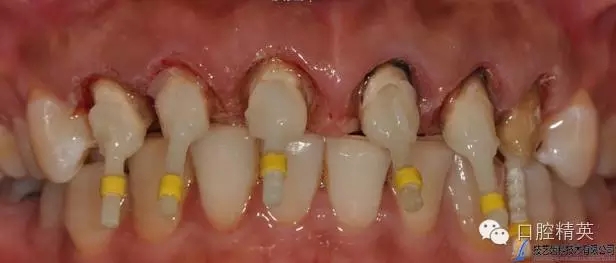

根管預(yù)備

PD纖維樁樹脂修復(fù)

水激光切除牙齦

臨時冠修復(fù)

牙體預(yù)備,精修,拋光。